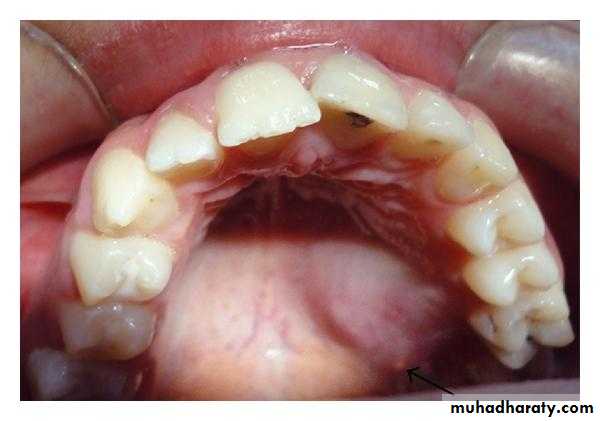

Intraorally, pleomorphic adenomas most often occur on the palate, followed by the upper lip and buccal mucosa.

Rare case of PA on the Buccal mucosa